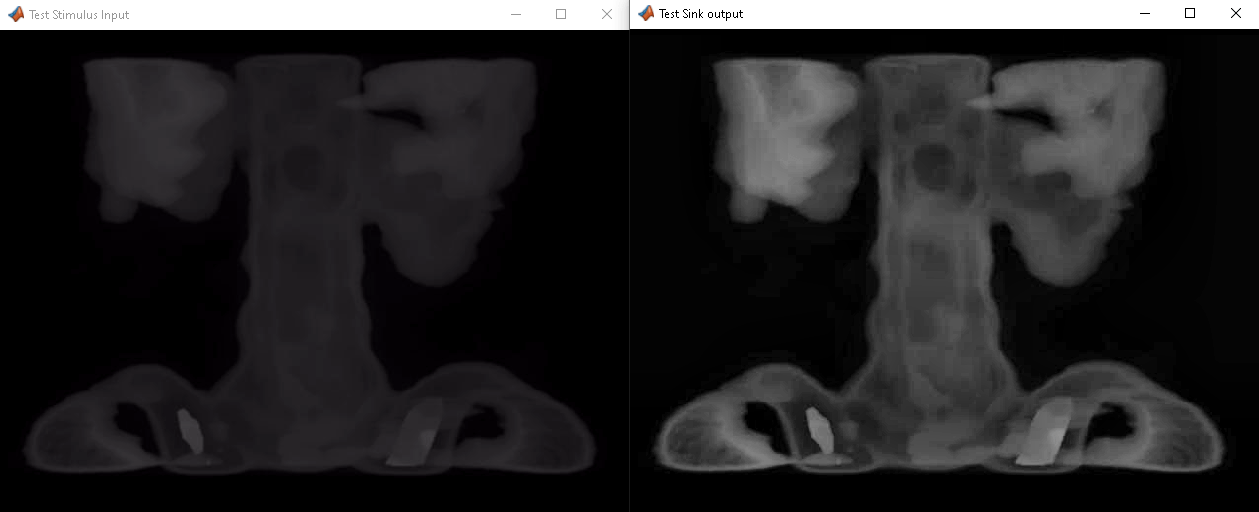

If you have an HDL Verifier license, you can use the FPGA-in-the-loop feature to prototype your HDL design on an FPGA board. The blocks on this page provide efficiency improvements for streaming pixel data across the Simulink® to FPGA board interface. HDL Verifier also enables you to cosimulate a Simulink model with an HDL design running in a third-party simulator.